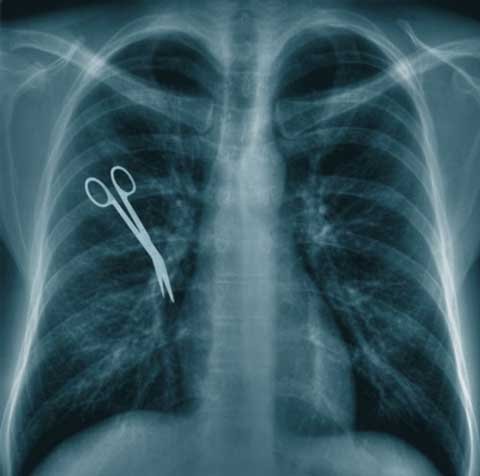

Anuj Ranjan, 20 tuổi, phải phẫu thuật để trị bệnh lao đã được chẩn đoán. Tuy nhiên, thay vào đó, các bác sĩ lại tìm thấy một chiếc thắt lưng da trong ngực chàng trai này, thứ mà Anuj quả quyết rằng nó đã chui vào người mình do một tai nạn ô tô khủng khiếp vào năm 2006.